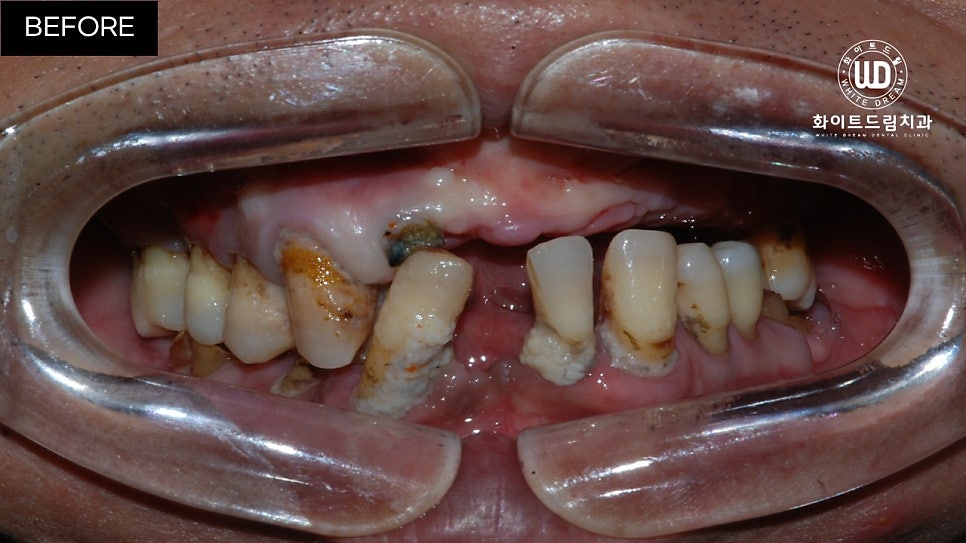

임플란트 식립 전 상, 하악 모습입니다.

육안으로 보이실지 모르겠으나 잔존한 치아 주위염이 심한 상태셨는데요. 뿐만 아니라 치아 파절과 함께 영구치의 뿌리 대부분이 손상되어 있는 상태였습니다.

이미 발치되어 있는 쪽은 치아가 소실된지 오랜 시간이 지나 잇몸뼈가 부족한 상태였고, 현 상태로는 픽스쳐를 식립할 수 없어 전체 발치 후 상악 양측 구치부 상악동 거상술 및 전체 치조골 이식을 동반한 전체 임플란트 식립을 진행하기로 했습니다.